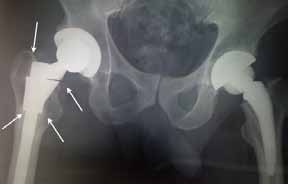

Apex Modular & Apex K2 Stem

- Modular junction failures = 0

- Dislocations = 3 (Two patients with MoM bearings have had cup revision due to cup spin out. One patient was one (1) year out with an ASR metal acetabular component. Patient presented with increasing groin and buttock pain. X-rays demonstrated that original cup position had changed and did not appear to be ingrown. The proximal modular junction of the K2 stem was disengaged allowing access to the socket. K2 removal instruments provide ease of removal of proximal modular body making cup revision signifi cantly easier with less bone destruction.

MoM cup spinout |

Revised with new cup & neck neck |

Second patient was female that presented a spun out MoM (Wright Medical) acetabular bearing component at her fi rst post-op visit at seven (7) weeks. Since intra-operative x-rays are taken on all patients it is assumed that cup slippage accrued during the early post-op period and then stabilized. Again the proximal modular junction was disengaged and cup removed with Explant system.

A new proximal modular neck and head were implanted with a cementless porous cup with one (1) screw for adjunct fi xation.

One additional patient had multiple dislocations and was revised by disengagement of the proximal modular junction and exchanged with an increased femoral offset and anterverted modular neck.